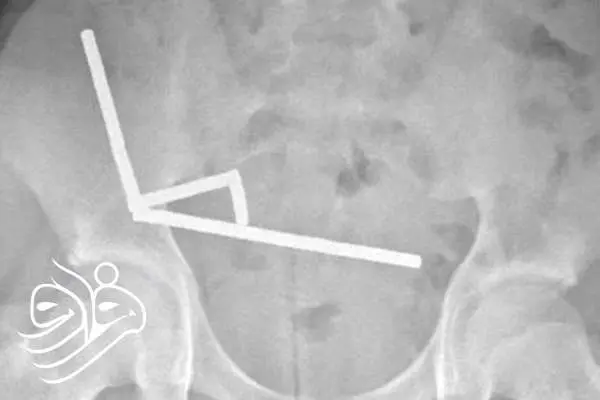

تصاویر رادیولوژی، چهار زنجیره بلند از آهنرباها را در بخش‌های جداگانه روده نشان داد. این ذرات فلزی کوچک درون بدن به هم متصل شده و باعث انسداد، پارگی و مرگ بخشی از بافت روده بر اثر فشار مغناطیسی شدند. در نهایت، پزشکان ناچار شدند بخشی از روده را خارج کنند.به گفته تیم درمان، وضعیت عمومی این نوجوان پس از عمل جراحی رضایت‌بخش است و او پس از هشت روز بستری، از بیمارستان مرخص شد.

زنجیره‌های آهنربایی در شکم نوجوان نیوزیلندی